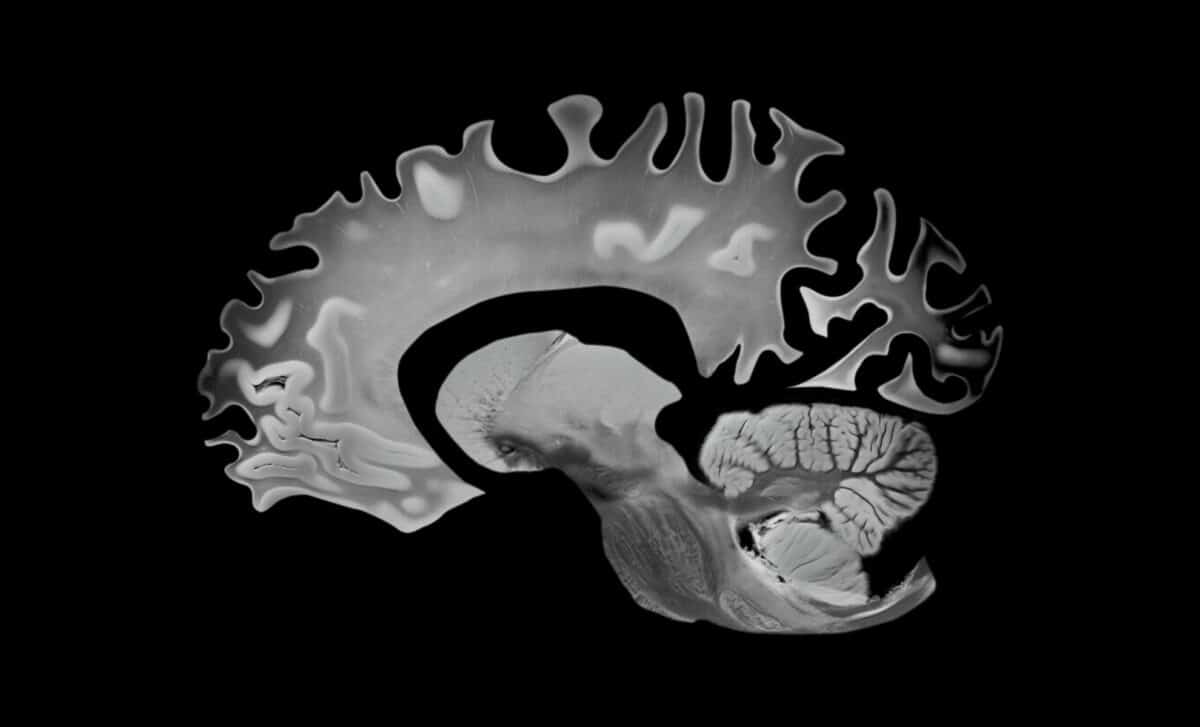

Over a median follow-up period of 12.3 years, researchers found that greater adherence to the MIND diet was linked to slower decline in total gray matter volume. Each three-unit increase in MIND diet score corresponded to a 0.279 cm³/year slower rate of gray matter loss, representing a 20.1% attenuation of age-related decline, equivalent to 2.5 years of reduced brain aging across the study period.

The implications don’t stop at gray matter. Higher MIND diet scores were also associated with slower expansion of lateral ventricular volume, a marker of brain tissue loss, reflecting roughly 8% to 8.8% attenuation of age-related changes, equivalent to approximately one year of delayed brain aging during follow-up.

To understand why these findings matter, it helps to understand what’s at stake biologically. Gray matter, rich in neuronal cell bodies, dendrites and synapses, plays a key role in memory, learning and decision-making. Ventricular expansion, by contrast, reflects brain atrophy, tissue loss accompanied by the enlargement of cerebrospinal fluid-filled spaces.

In other words, both markers tracked in this study are well-established signals that the brain is shrinking in ways that eventually translate into cognitive decline.

Brain Scans Vs. Diet How 12 Years Of Mri Data Revealed The Mind Diet's Effect On Aging. © Journal Of Neurology Neurosurgery & PsychiatryBrain Scans vs. Diet: How 12 Years of MRI Data Revealed the MIND Diet’s Effect on Aging. © Journal of Neurology Neurosurgery & Psychiatry